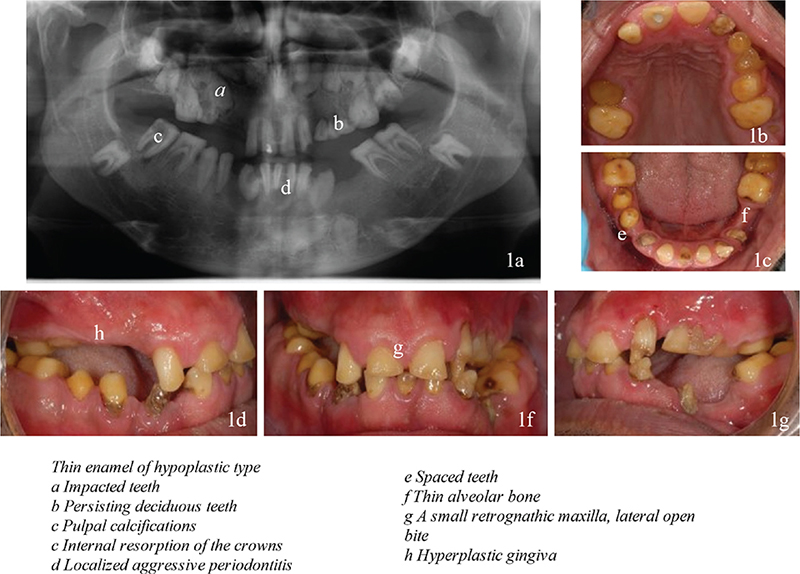

Renal follow-up and outcome

The first CT scan of the kidneys showed bilateral multiple small medullary calcium deposits in the renal calyces consistent with nephrocalcinosis (Figure 6). In a later CT scan after 6 years, the degree of nephrocalcinosis had not changed. A DXA bone densitometry showed normal values: T- and Z-scores were -0.6 and 0.3, respectively in the lumbar spine, and -0.4 and -0.1, respectively in the hip. The blood samples showed marked hypophosphatemia, borderline elevated p-alkaline phosphatase, slightly elevated p-PTH and p-FGF-23, low p-25-OH-vitamin D, hypocalciuria and hypocitraturia (Table 1). Plasma levels of calcium, magnesium, urate, bicarbonate, creatinine, eGFR, and 1,25-OH2-vitamin D and urinary levels of magnesium, urate, oxalate, and albumin were normal.

Figure 6

Figure 6. Bilateral nephrocalcinosis. Bilateral nephrocalcinosis in computed tomography (red arrows).

Presently, the patient has regular check-ups at the Nephrology Unit. The renal function has remained unaltered and normal. The blood and urine values have remained at the same levels. Because of low urinary citrate, potassium citrate was prescribed to increase urinary citrate levels, which decreases the risk of progressive renal stone formation. Seven years after the initial investigation, the patient suffered his first kidney stone attack. Increased water intake and intensified potassium citrate treatment were commenced.